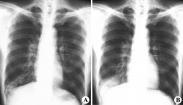

• 支氣管擴張

628健康網為您分享有關支氣管擴張的癥狀,支氣管擴張的治療方法,支氣管擴張的預防知識,支氣管擴張的癥狀圖片,支氣管擴張...